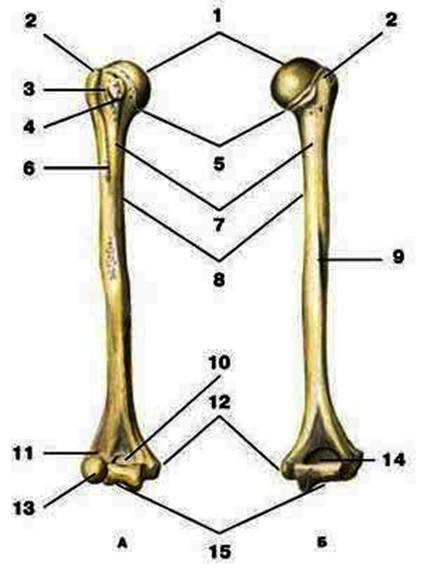

S: Цифра 1 обозначает головка плечевой кости.

S: Число 15 обозначает блок плечевой кости.

S: Цифра 5 указывает на хирургическая шейка плечевой кости.

S: Число 10 обозначает венечная ямка плечевой кости.

S: Число 14 указывает на локтевая ямка плечевой кости.

S: Цифра 9 указывает на борозда лучевого нерва плечевой кости.

S: Число 12 обозначает медиальный надмыщелок плечевой кости.

S: Стрелка указывает на большой бугорок плечевой кости.

S: Стрелка указывает на малый бугорок плечевой кости.